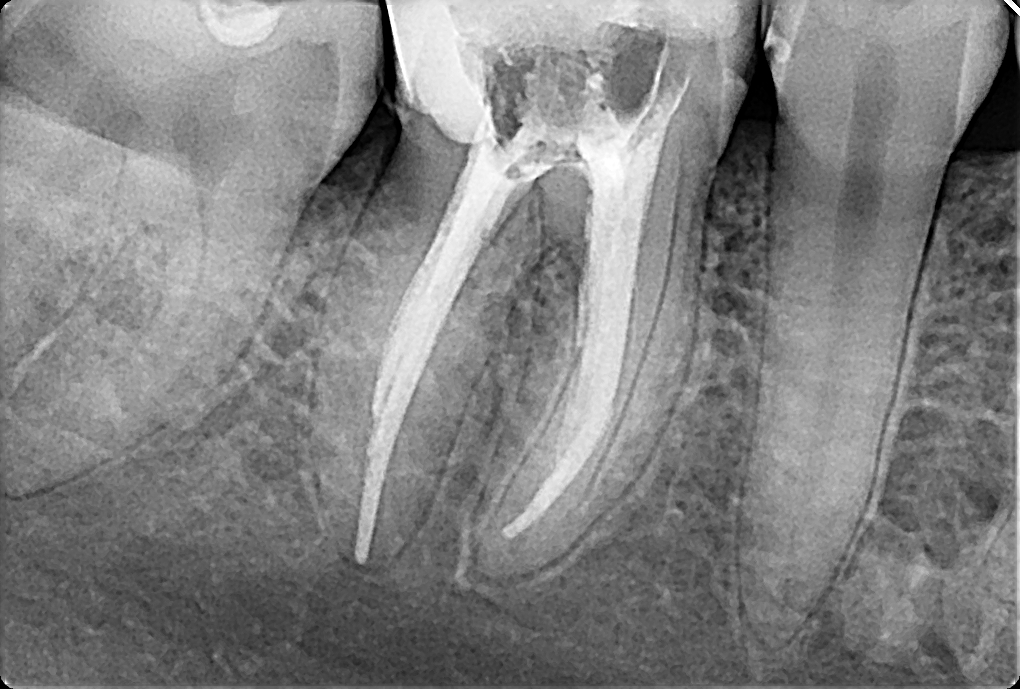

Прицільна рентгенограма –  це невеликий знімок, що охоплює 2-3 зуби. Через низьку дозу опромінення, доступність та швидкість проведення цей метод дослідження є самим поширеним. Така діагностика проводиться звичайно перед видаленням зуба, до та після лікування кореневих каналів, а також для виявлення карієсу або периапікальних запальних змін, невидимих при стандартному стоматологічному огляді.

Прицільний рентген-знімок